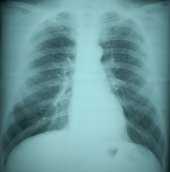

CHEST RADIOGRAPHY

B Reader approval is granted to physicians with a valid U.S. state medical license who demonstrate proficiency in the classification of chest radiographs for pneumoconioses using the International Labour Office (ILO) Classification System.

Proficiency is evaluated via the B Reader Examination, which was developed in response to the mandates of the Federal Mine Safety and Health Act. Since the examination was first administered in 1974, more than 1000 physicians have passed it. Currently, there are about 300 B Readers ( Current B Reader List ).